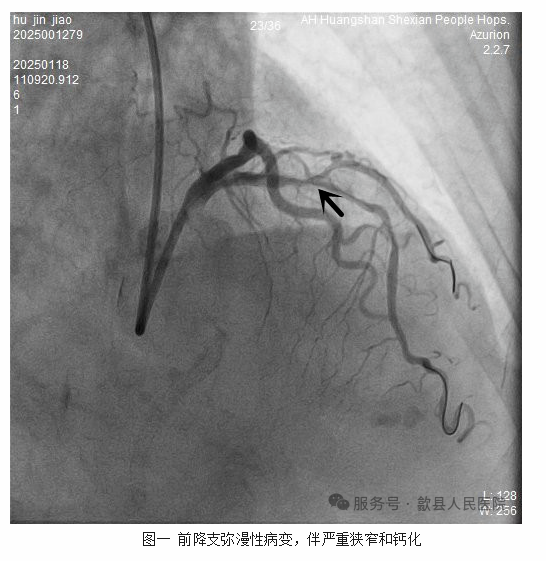

患者此次为处理前降支病变入院,在完善术前相关检查和评估后。1月18日胡奶奶被送入导管室进行了冠脉造影。检查提示左侧前降支血管为弥漫性长病变,最狭窄的地方接近90%,且在造影剂不填充的情况下就可以明显地看到血管里的“石头”,钙化十分严重(图1)。